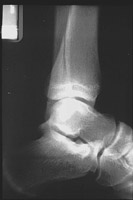

The triplane fracture is also known as the Marmor-Lynn fracture and typically occurs in adolescents. The term actually refers to three fractures of the tibia: a vertical fracture through the epiphysis, a horizontal fracture through the physis, and an oblique fracture through the metaphysis. Twisting injuries produce this type of fracture.

- Click on the image for a larger versionBLateral radiograph of the ankle. The metaphyseal fracture line is visible within the tibia.